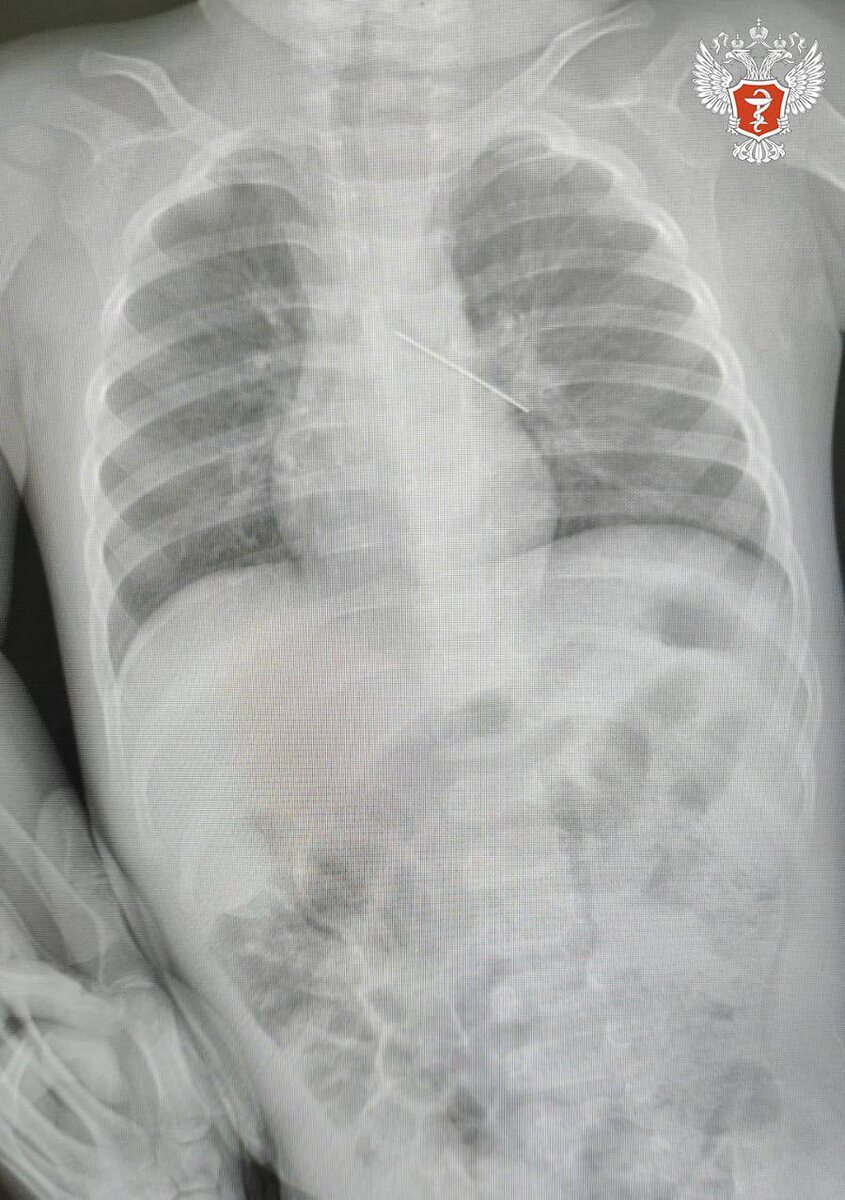

И снова булавка: врачи в Ханты -Мансийске спасли малыша с инородным телом в бронхах

Ребенок поступил по скорой помощи в Сургутский окружной центр охраны материнства и детства после того, как мама заметила опасность. В ходе обследования врачи установили, что инородное тело оказалось в бронхах — одном из наиболее опасных мест при подобных ситуациях.

Возникла угроза развития тяжёлых осложнений, включая полную закупорку дыхательных путей.

"Ситуация была предельно серьезной. Если бы бригада наших высокопрофессиональных специалистов не смогла удалить инородный предмет с помощью бронхоскопа, ребенка пришлось бы передавать торакальным хирургам для проведения большой операции", - отметили в медицинском центре.

Специалисты выполнили эндоскопическое вмешательство и успешно извлекли булавку с помощью бронхоскопа. Бронхоскоп — это инструмент в виде тонкой гибкой или жёсткой трубки диаметром от 3 до 6 мм, с помощью которого врач осматривает слизистую оболочку бронхов.